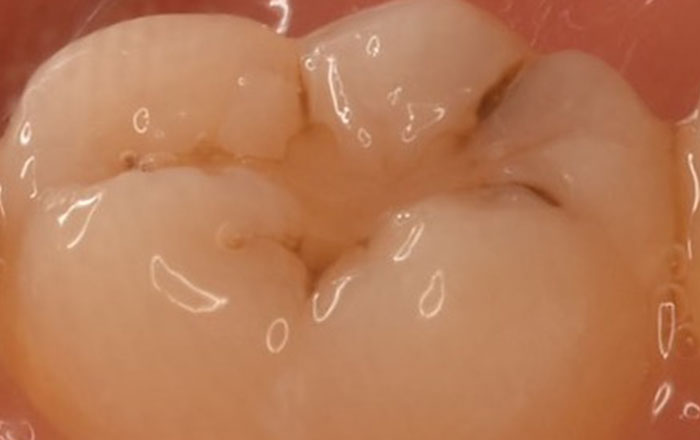

2.C1のむし歯

C1のむし歯は、エナメル質までむし歯が達している状態です。

初期むし歯(CO)が進行して、歯の一番外側のエナメル質の表面に穴が空いています。この段階も、まだ痛みはありません。